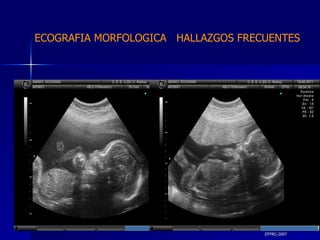

DTFRC-2007 ECOGRAFIA MORFOLOGICA  HALLAZGOS FRECUENTES   MATERIAL Y METODO ES UN ESTUDIO DESCRIPTIVO, RETROSPECTIVO  DE ESTUDIO ECOGRA FICOS REALIZADOS ENTRE MARZO 07 A MARZO 08 EQUIPO DE ALTA RESOLUCION   VOLUSON 730 PRO  MEDISON SA 8000 live MEDISON SA 8000SE CRITERIO DE INCLUSION:   POBLACION GENERAL    GESTACIONES  20 a 24 SEMANAS   UNIVERSO  N 211

DTFRC-2007 ECOGRAFIA MORFOLOGICA  HALLAZGOS FRECUENTES   GENITOURINARIA DISPLASIA RENAL MULTIQUISTICA  3 HIDRONEFROSIS  2 QUISTE DE OVARIO FETAL  1 SISTEMA DIGESTIVO DILATACION INTESTINAL  2  SISTEMA ESQUELETICO   PIE BOT  2  20 % 6 % 6 %

DTFRC-2007 ECOGRAFIA MORFOLOGICA  HALLAZGOS FRECUENTES   OTROS HIGROMA QUISTICO  2 ENFERMEDAD ADENOMATOSA PULMONAR  1 ARTERIA UMBILICAL UNICA  2 HIDROPS FETAL NO INMUNE  1 QUISTE DE CORDON UMBILICAL  1 ALTERACION DE LIQUIDO ANMIOTICO  2 SINDROME TRAFUSIONAL FETO FETAL 1 LABIO LEPORINO  2 TOTAL  12  42 %